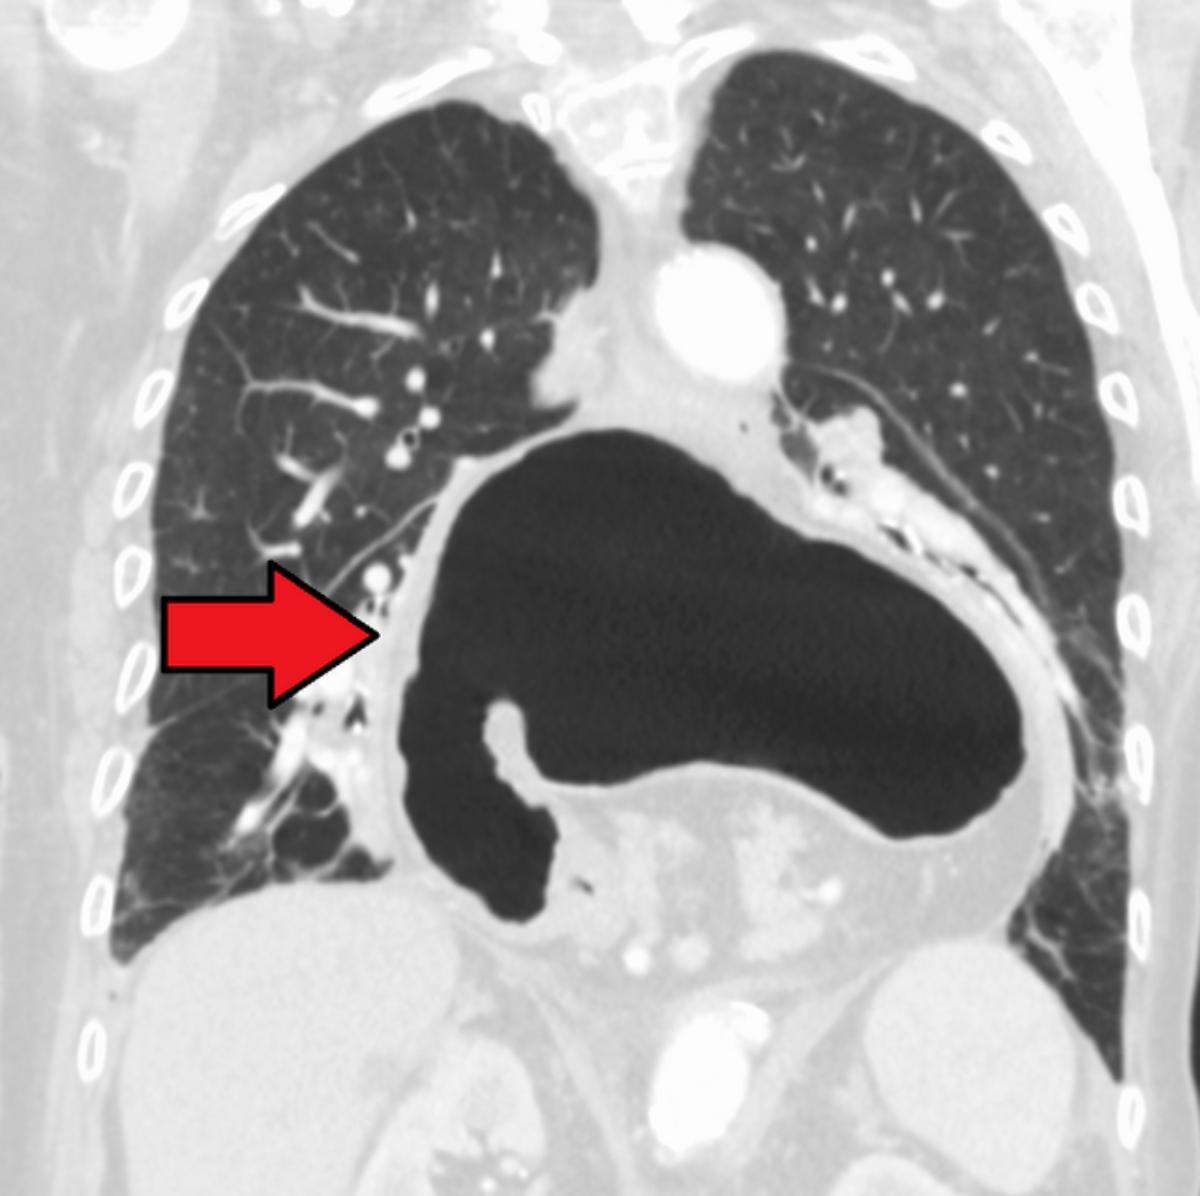

El hiato es un orificio situado en el diafragma que permite el paso del esófago hasta el estómago. Su función es importante ya que impide que el contenido del estómago refluya hasta el esófago. ¿Pero qué pasa cuando aparece una hernia en esta zona?

Pues al debilitarse o desplazarse esta zona parte del estómago se introduce o se hernia a través del hiato hacia el espacio torácico, provocando diversos síntomas o no. Porque hay pacientes que tienen hernia de hiato pero que no registran ninguna molestia, en cambio otros si sufren uno de los síntomas más habituales de esta patología: el reflujo.

- Hernia hiatal por deslizamiento: se produce cuando el estómago sube hasta la cavidad torácica.

- Hernia hiatal paraesofágica: cuando el deslizamiento del estómago se produce de forma paralela al esófago